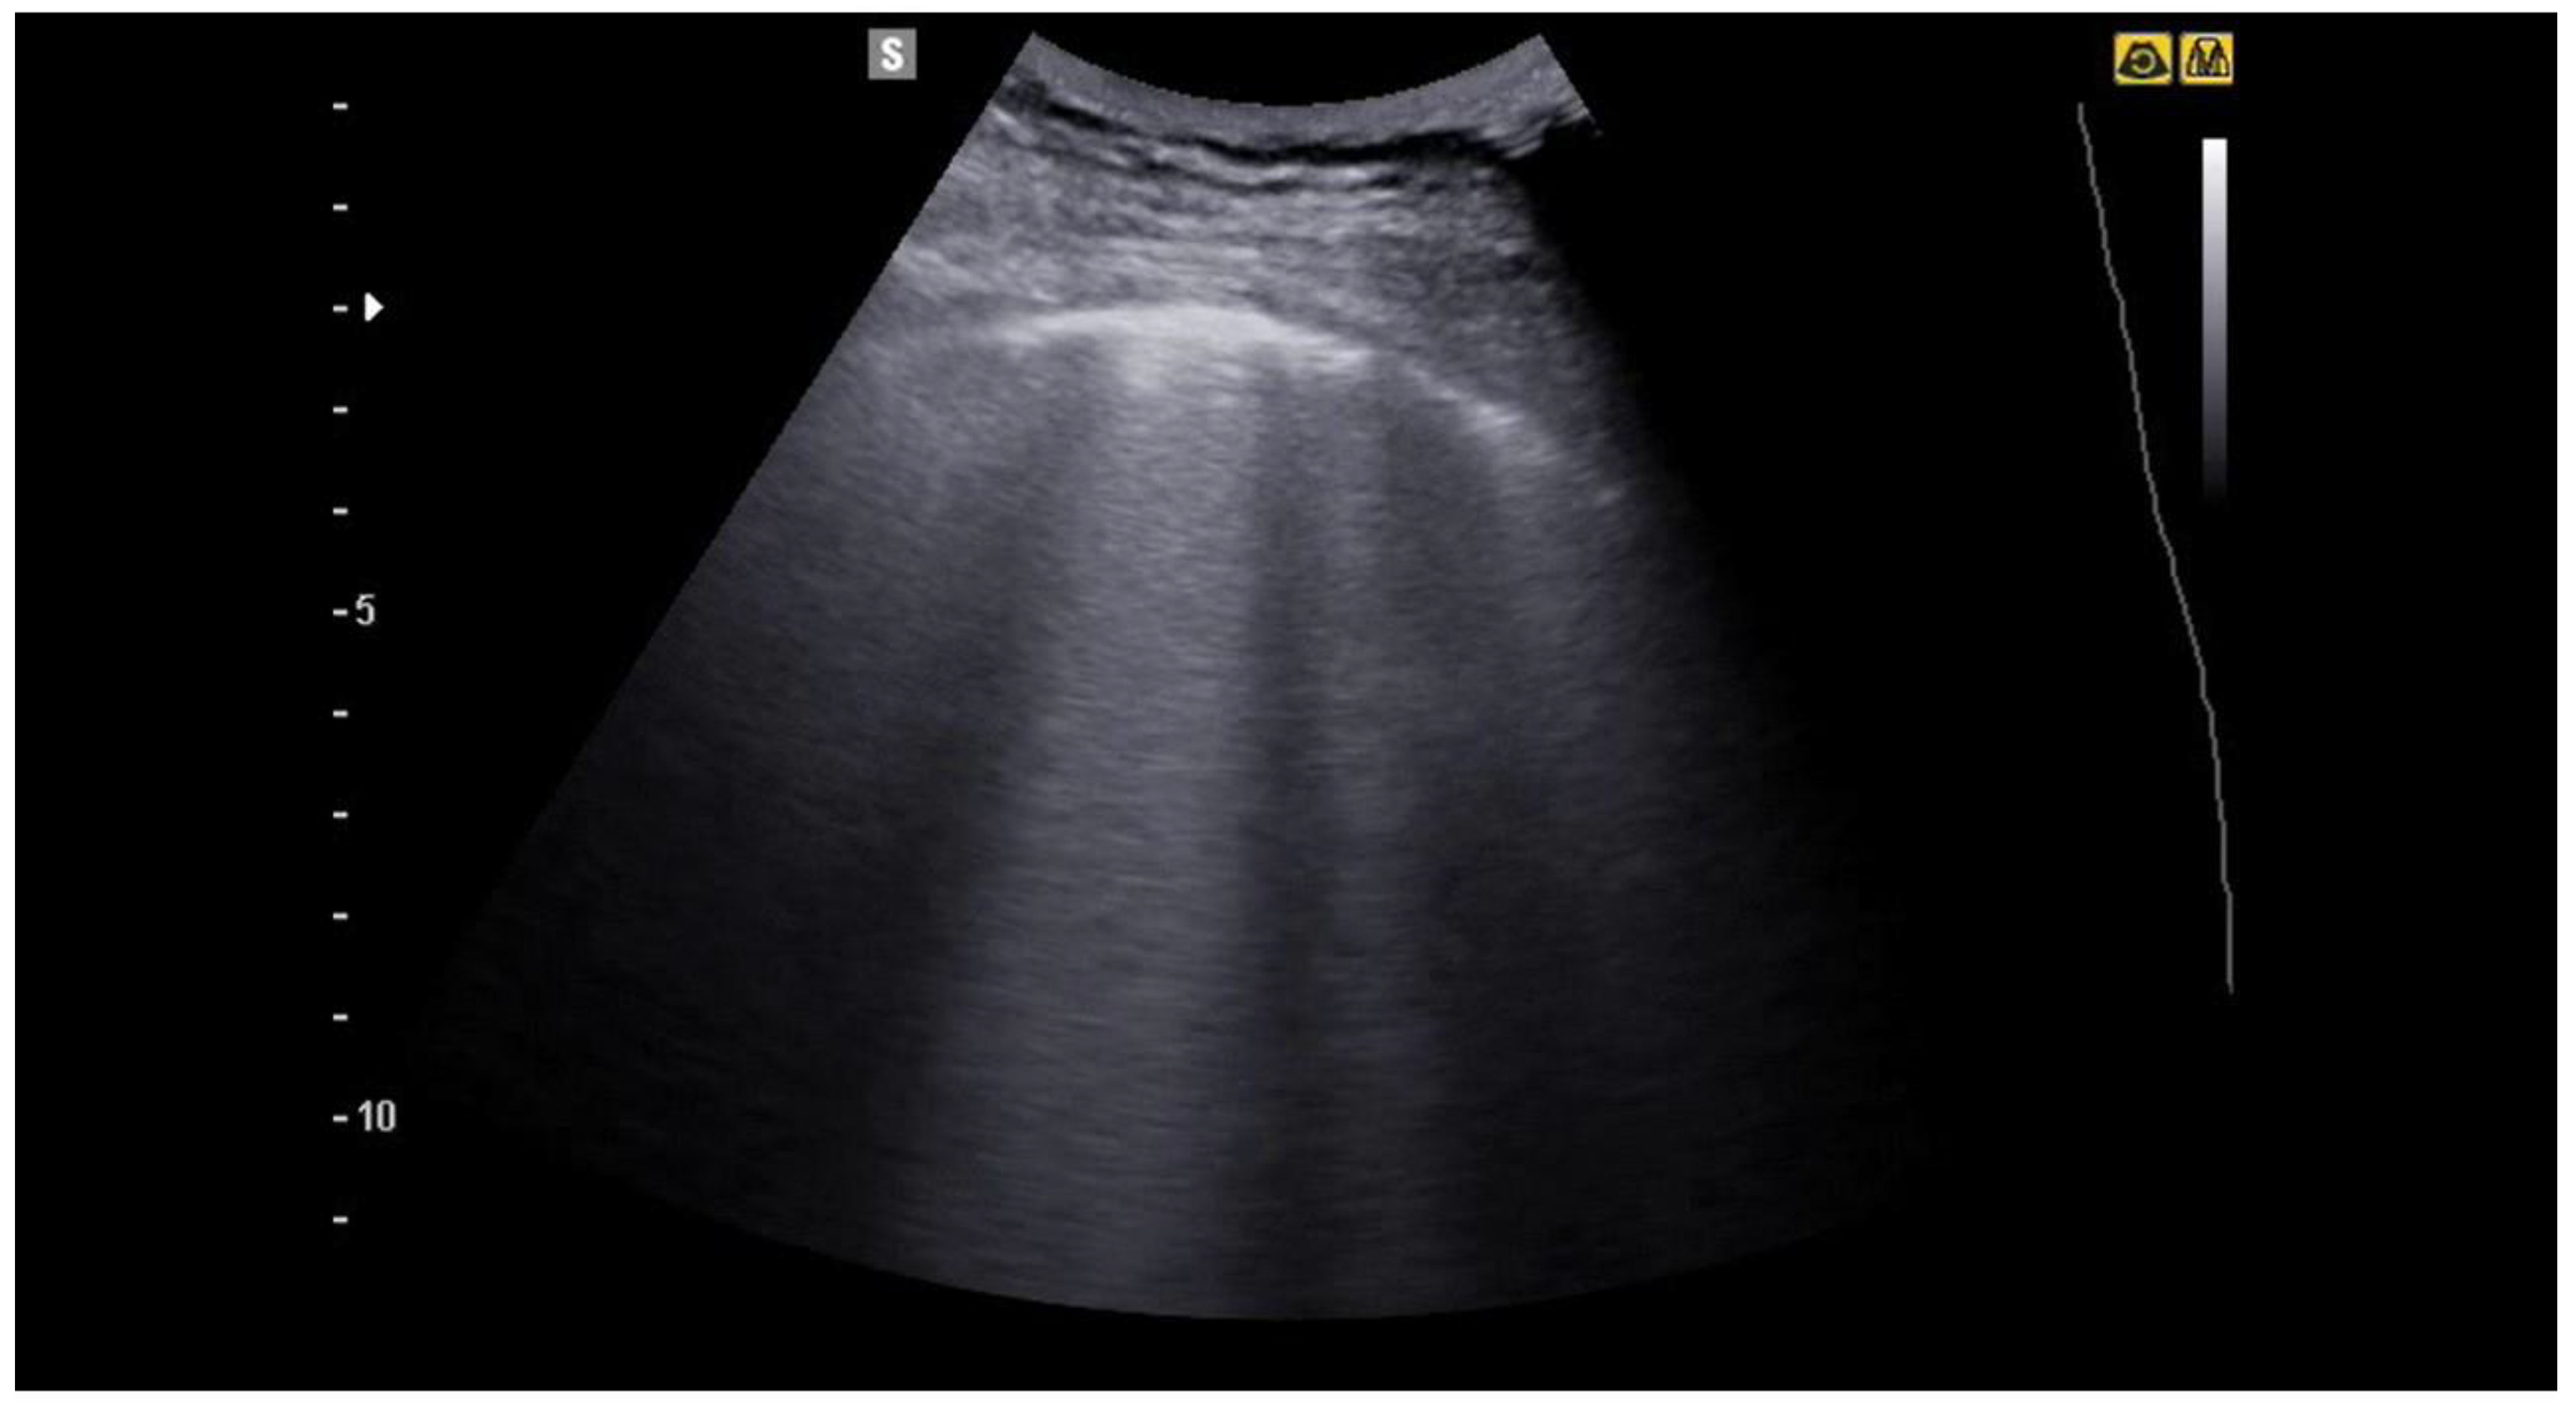

4. Lung Ultrasound on Physiological Lung